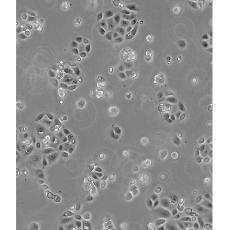

SW 1990

產品名稱 SW 1990

中文名稱 人胰腺癌細胞

細胞數量 1*10^6

細胞種屬 Homo sapiens, human

生長特性 adhere

形態特征 epithelial

細胞描述 1978年從胰腺外分泌腺的胰腺腺癌II期患者的脾轉移灶中建立了SW 1990細胞株。 報道該細胞的植板率為29%。